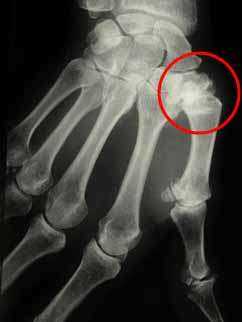

X-ray examination of thumb osteoarthritis

Rhizarthrosis is osteoarthritis of the base of the thumb. This condition is also called “trapeziometacarpal osteoarthritis.” It corresponds to chronic cartilage wear between the trapezium (a wrist bone) and the first metacarpal (thumb bone).

An X-ray assessment is requested to confirm the diagnosis of rhizarthrosis.